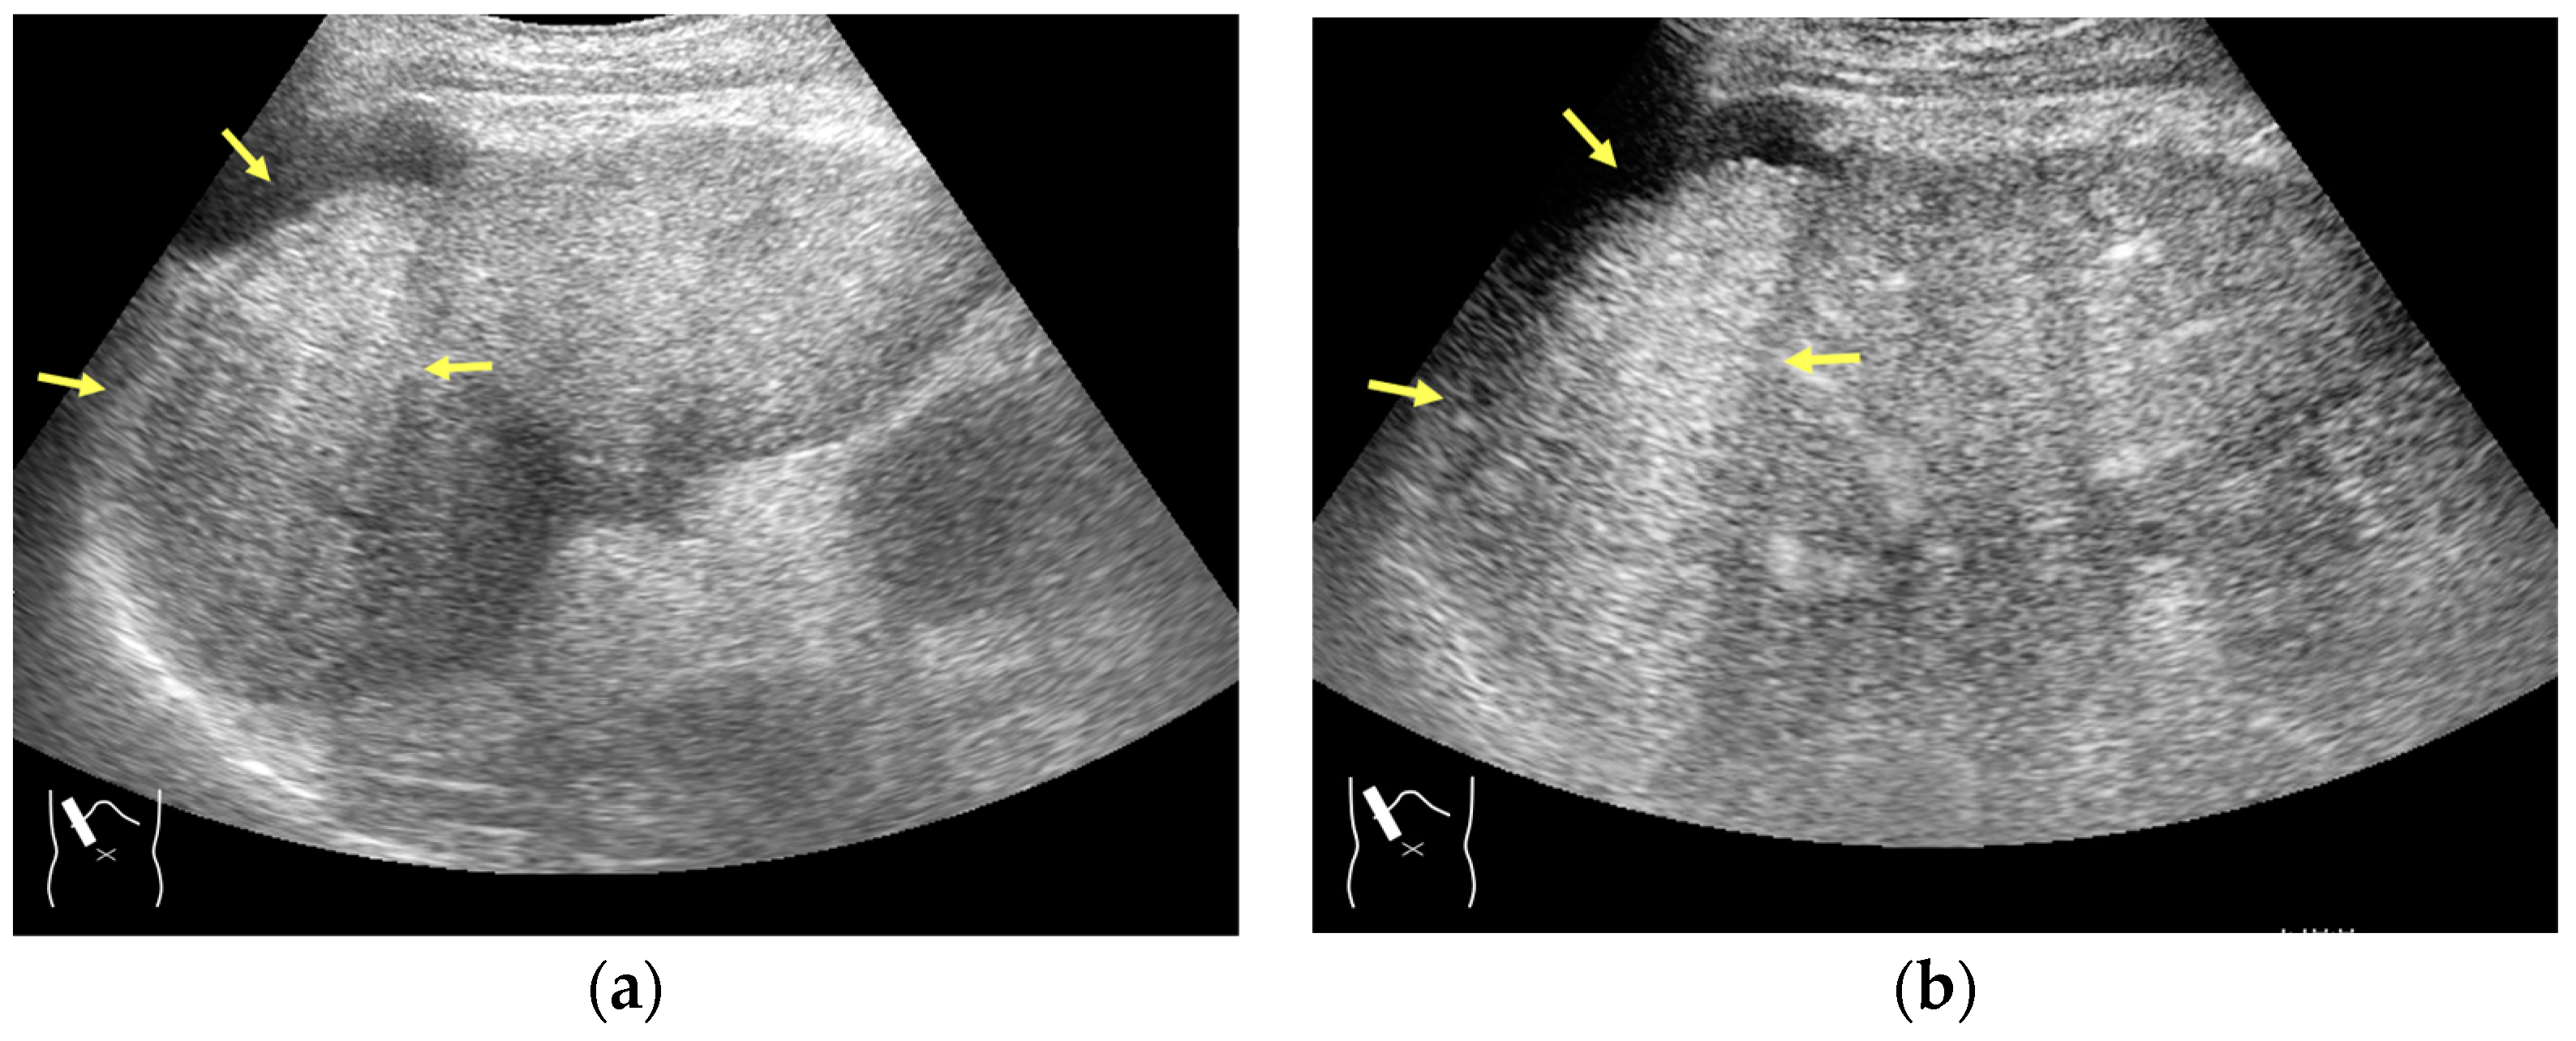

3.1.1. Refraction Artifacts

- Naganuma, H.; Ishida, H.; Uno, A.; Nagai, H.; Ogawa, M.; Kamiyama, N. Refraction artifact on abdominal sonogram. J. Med. Ultrason. 2021, 48, 273–283. [Google Scholar] [CrossRef]